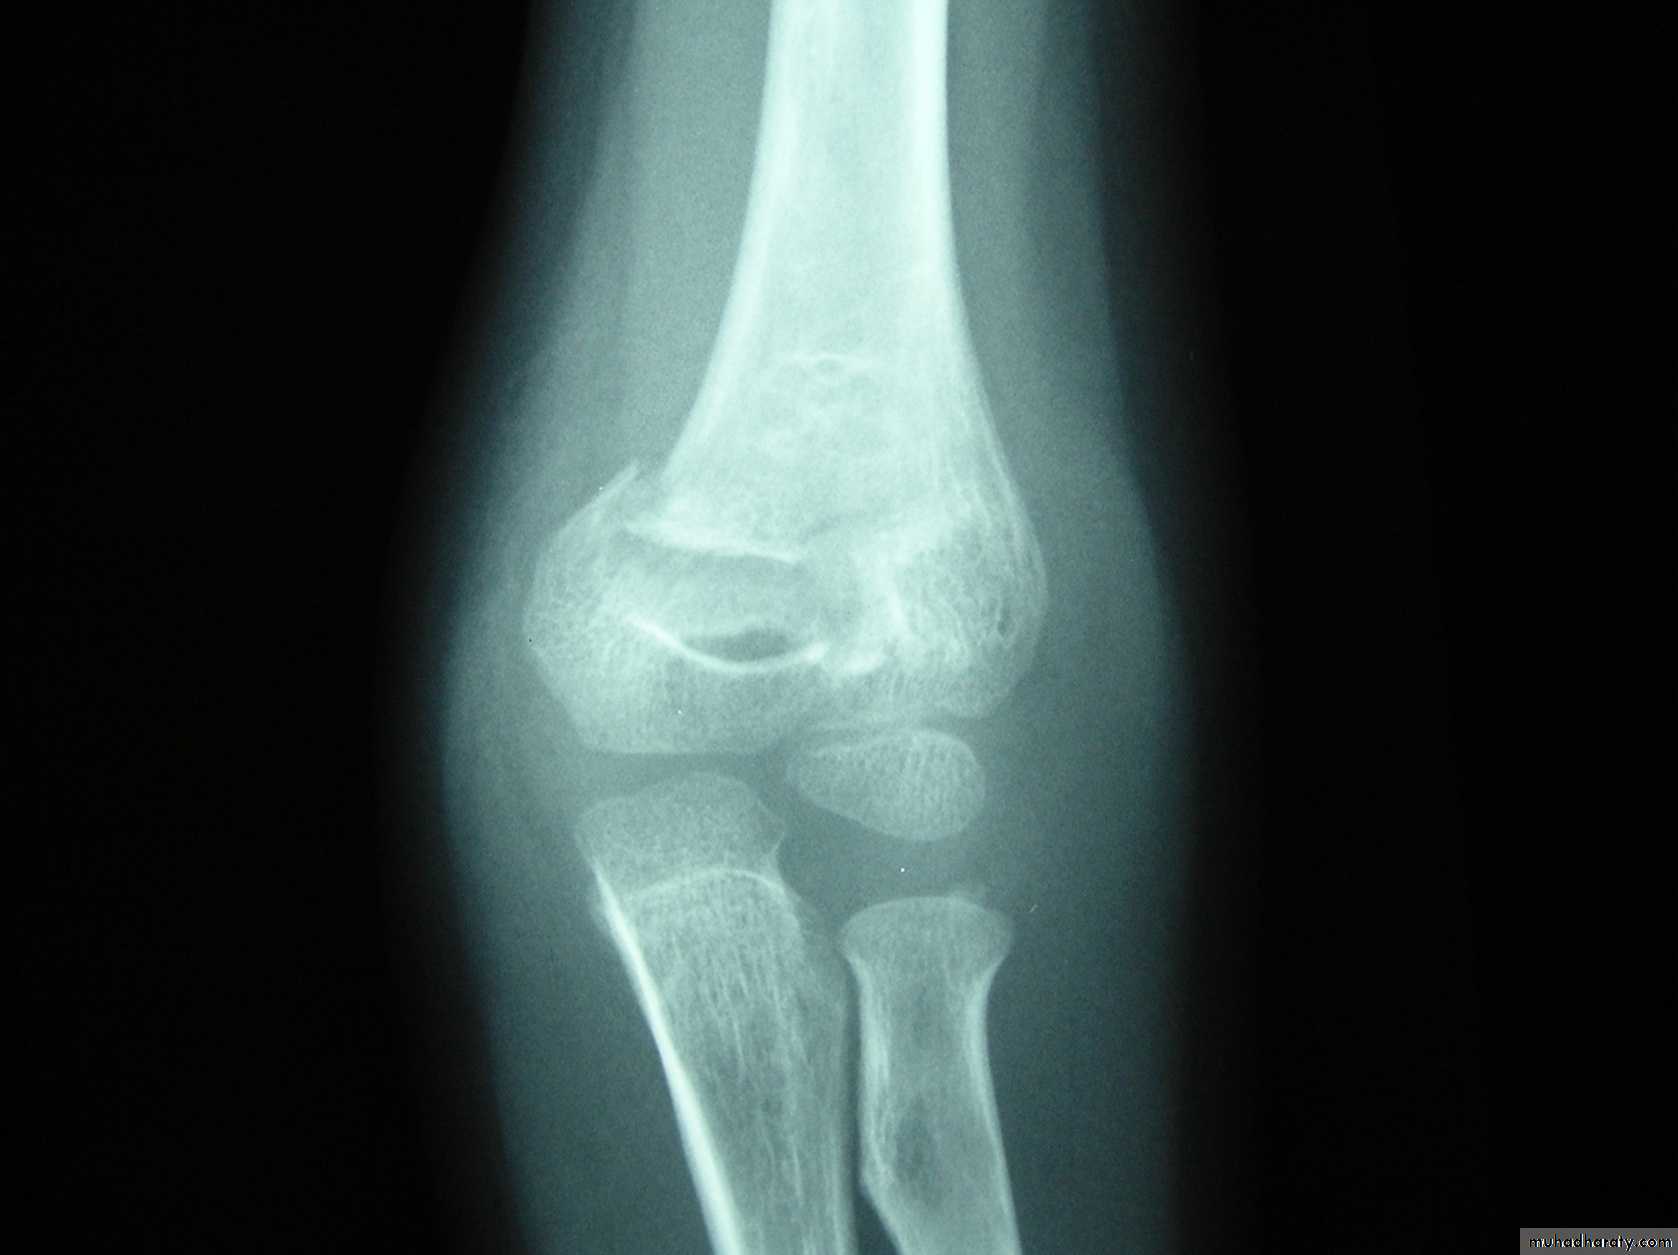

This classical Type III pattern

8 y.o.

Is this a simple extension

type supracondylar fracture ??

It also has

anterolatateraldisplacement !!

The distal fragment is

not flexed,but also it is not extended to any degree.

This also is a Type III Flexion Pattern.